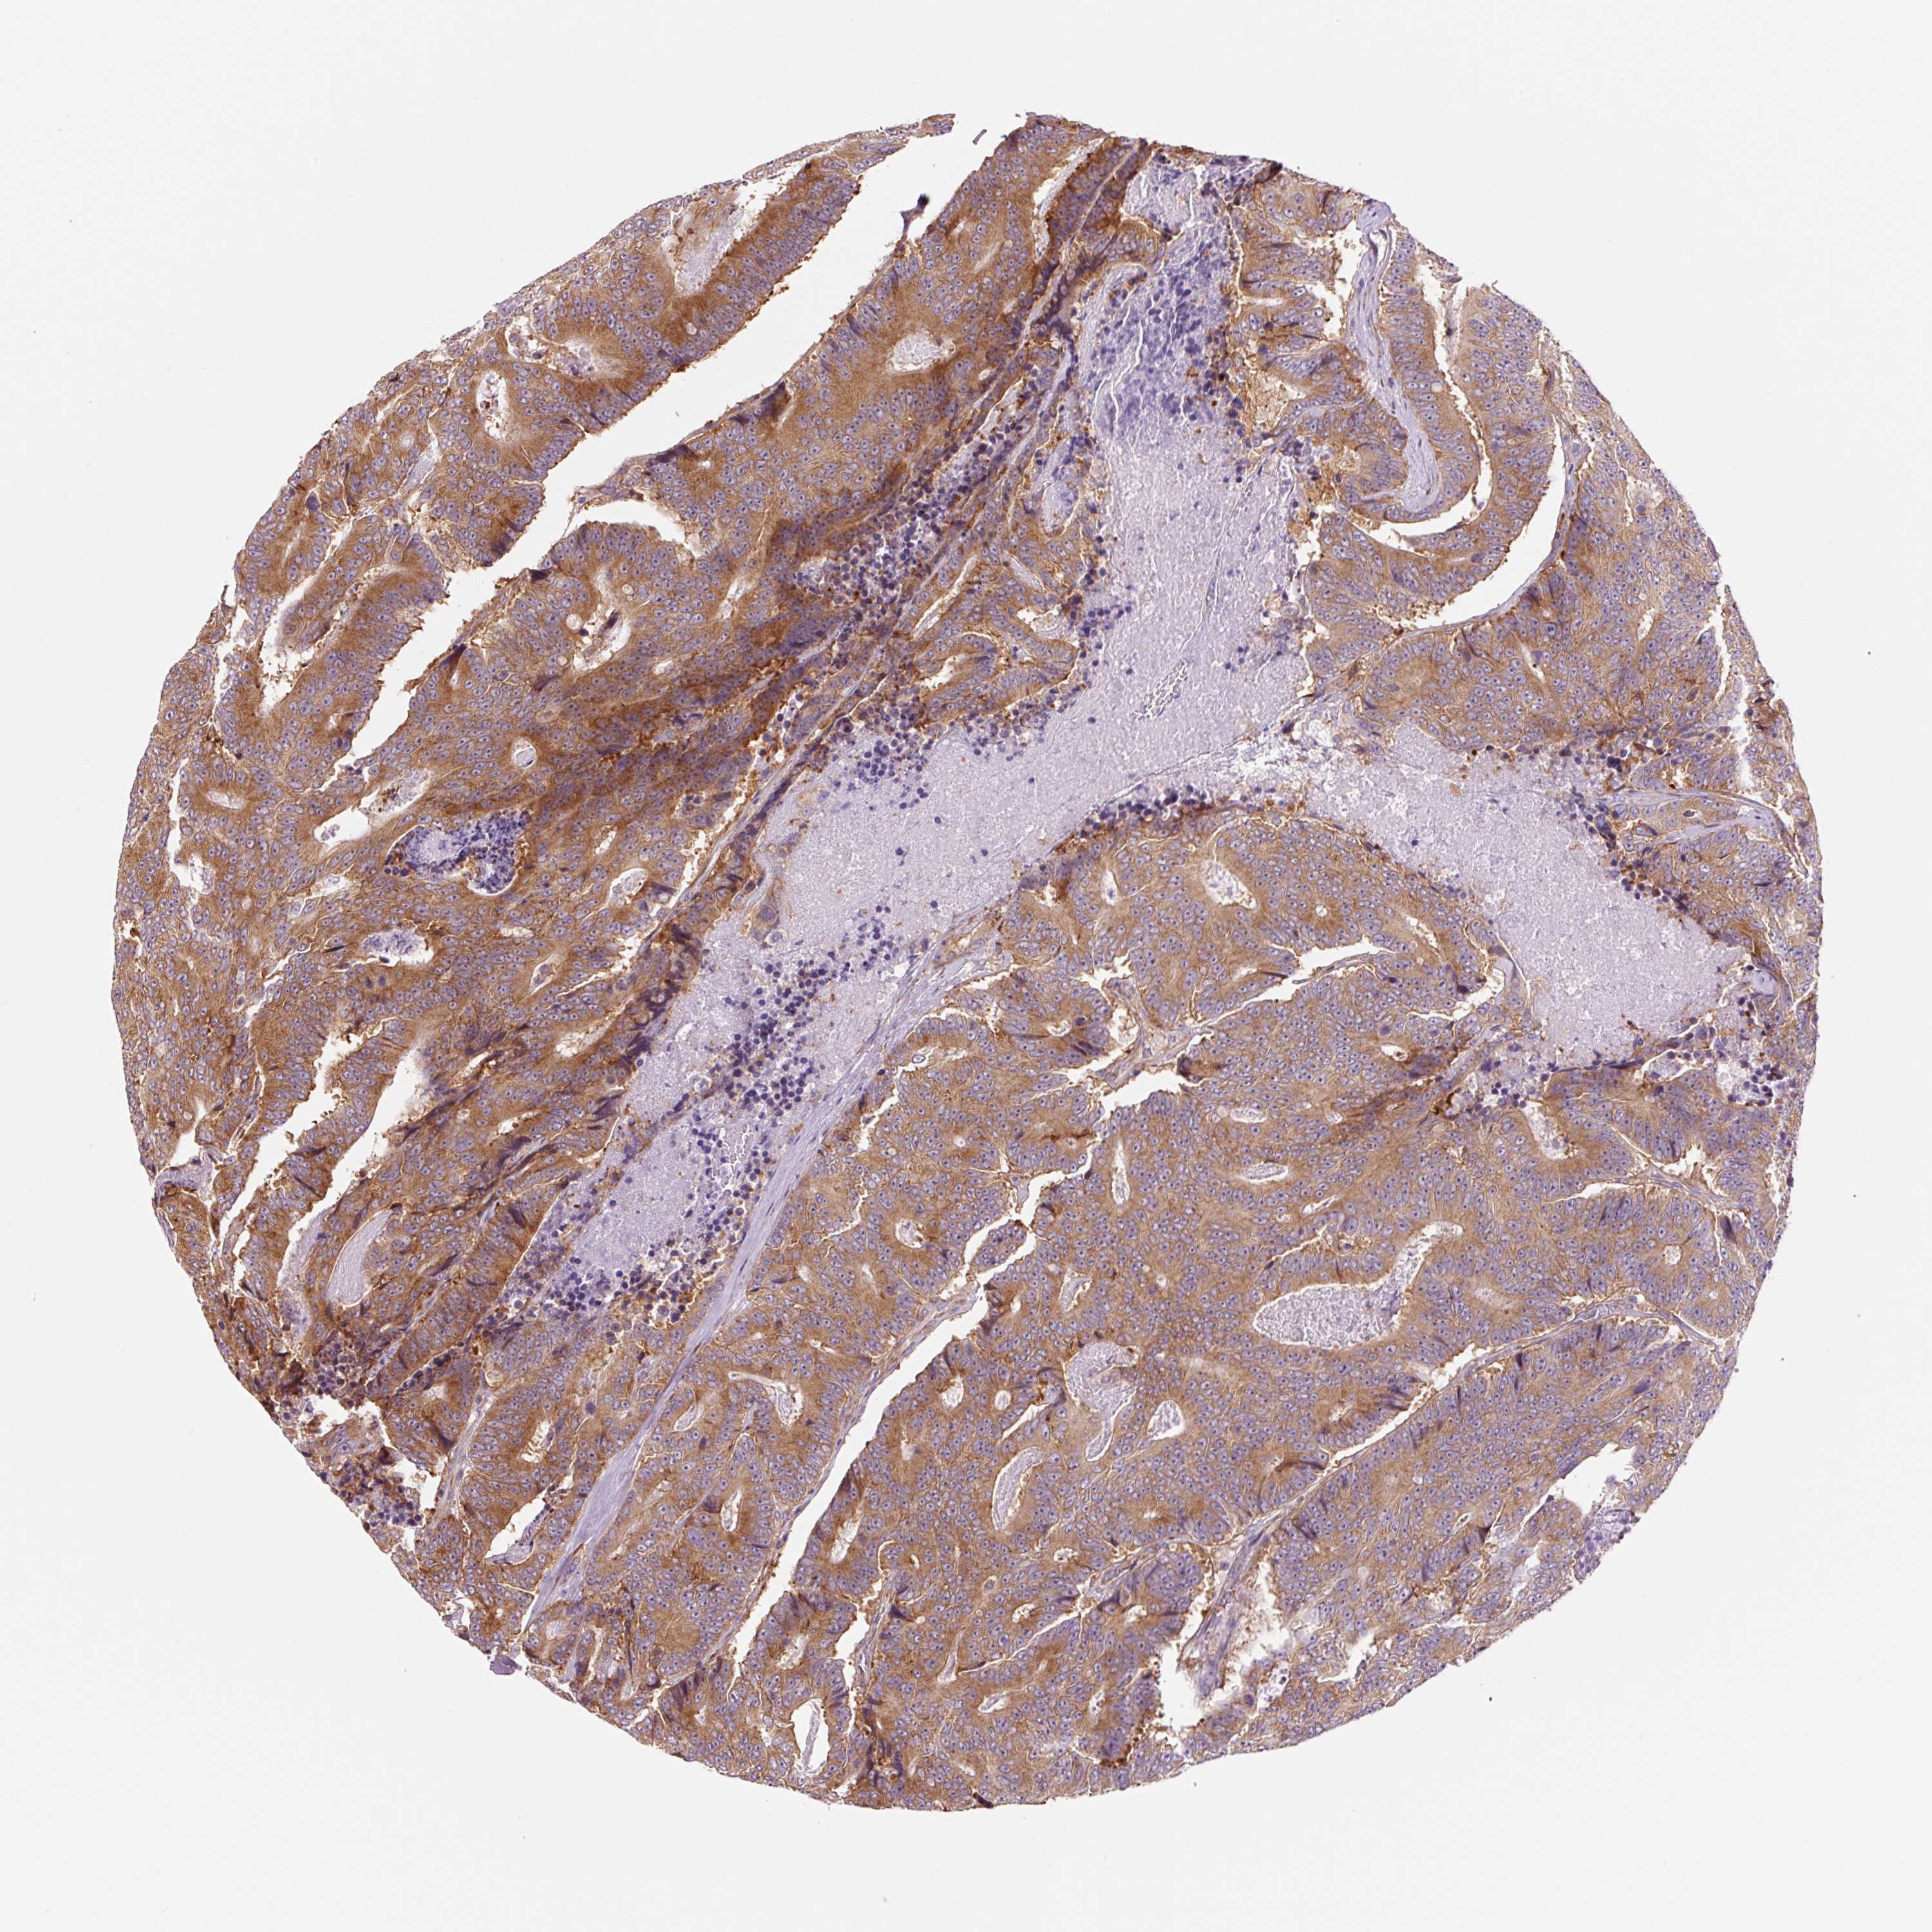

CANCER COLORECTAL CANCER Show tissue menu

Colorectal cancer

Human cancer

Colon adenocarcinoma

Rectum adenocarcinoma